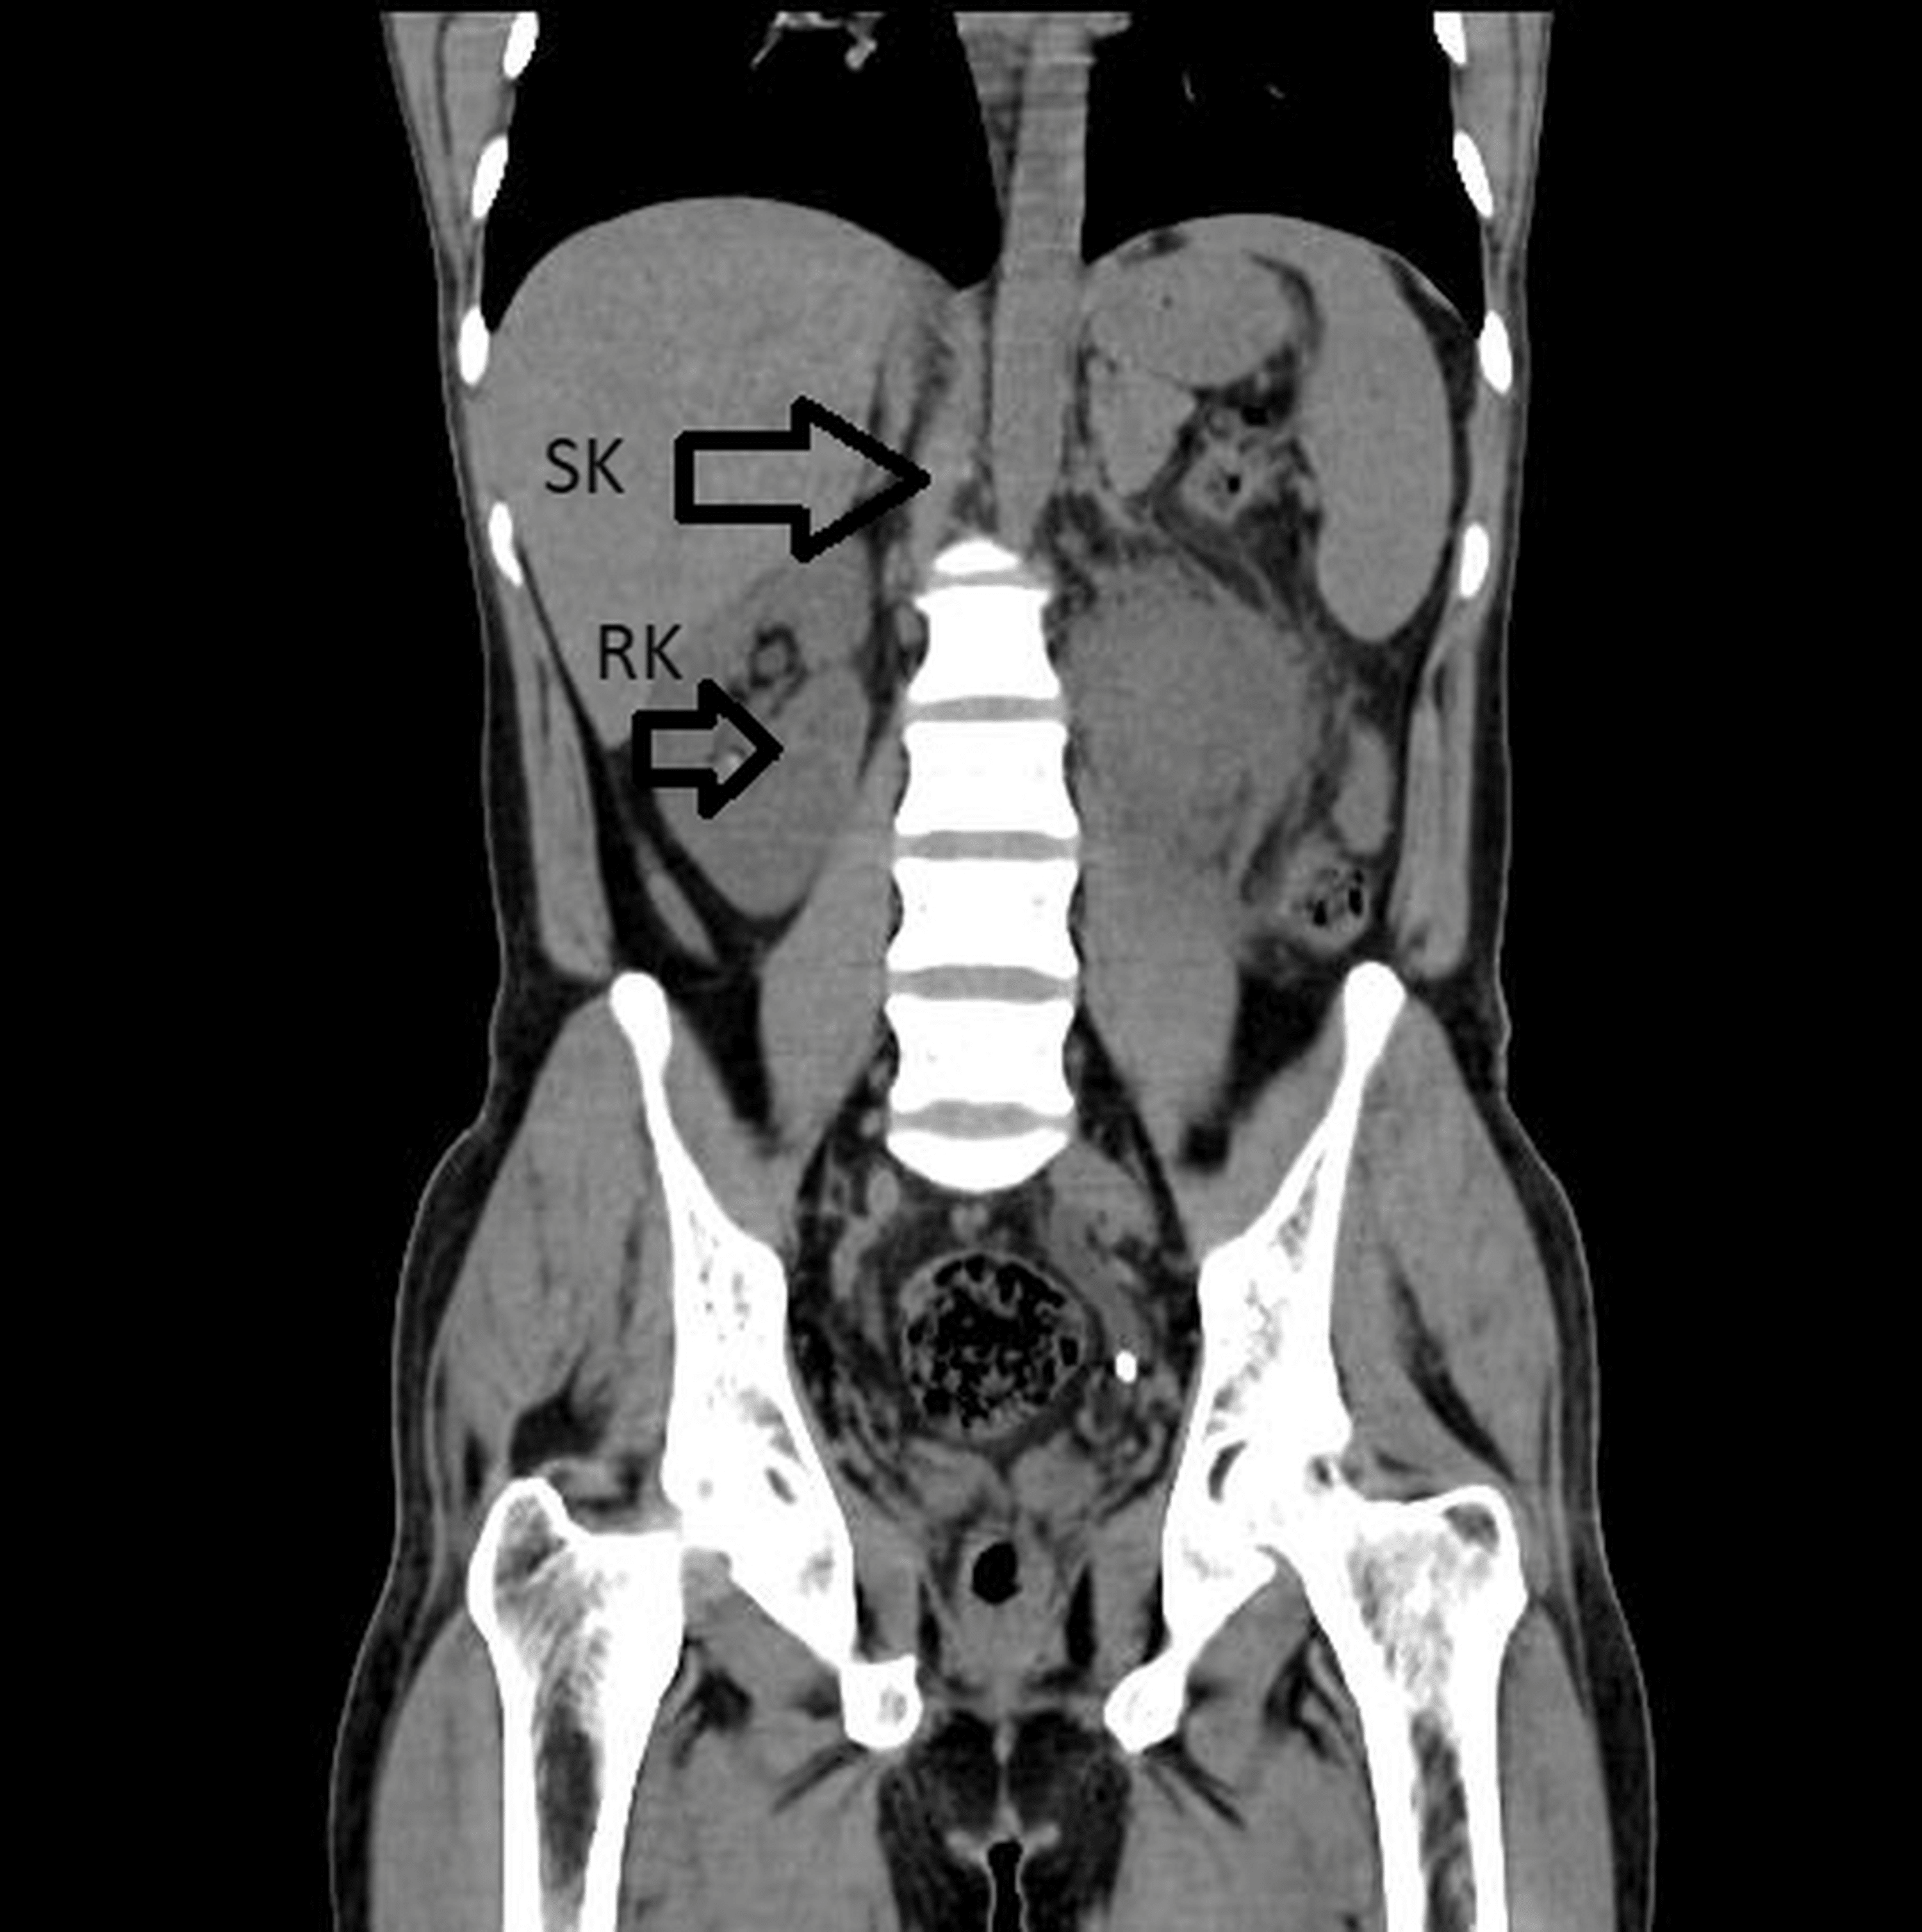

Cureus Supernumerary Kidney (Triple Kidney) With Horseshoe

From www.cureus.com